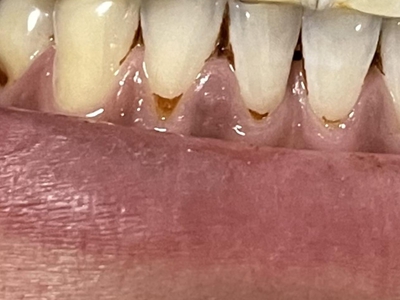

楔状缺损症状图片

楔状缺损是一种非龋性牙颈部慢性损伤,是指发生在牙齿唇、颊面颈部的慢性硬组织缺损。典型缺损由两个夹面组成,口大底小,呈楔形。楔状缺损多发生于中老年人,主要原因是刷牙不当,防治措施是调整咬合关系,改善刷牙方法,配合相应的治疗。

楔状缺损与年龄相关,即年龄越大,缺损越重,患者多有横刷牙习惯,患牙为多颗甚至全口,常以口角附近的牙齿(尖牙、前磨牙)为重。典型表现为牙颈部缺损,呈楔形,由两个夹面组成,口大底小,缺损处质地坚硬,表面光滑,边缘整齐,无染色,轻微泛黄常为牙齿本色,严重时可导致牙髓腔暴露甚至牙齿横向折断,根据缺损深浅不同,可伴有牙齿敏感甚至疼痛。